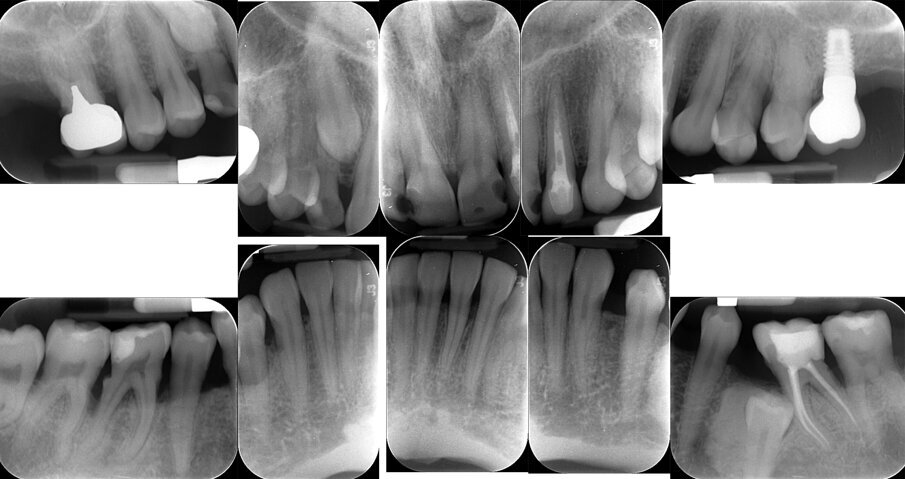

Viene perciò effettuata una visita parodontale completa con compilazione della cartella parodontale, set fotografico e raccolta dello status radiografico. Il profilo di rischio parodontale della paziente, stilato in base ai criteri del Periodontal Risk Assessment1 risulta essere di tipo “alto”. Vista la perdita di attacco clinico (CAL) nel sito con maggiore interessamento (≥5 mm), la perdita ossea valutata radiograficamente (RBL), la progressione della malattia (valutata “moderata”), la diagnosi è di Parodontite Generalizzata di Stadio IV e Grado B2. Osservando la cartella parodontale si può notare una maggiore progressione della malattia nei sestanti III, IV e VI con sondaggi superiori ai 6 mm a carico degli elementi 2.4, 3.6, 3.7, 4.4, 4.5, 4.6. e 4.7, BOP (Bleeding on Probing) positivo e SOP (Suppuration on Probing) positivo nei siti 2.4. e 4.6.

Fig. 3 - Status radiografico al T0.

Fig. 5 - Rx peri-apicale dell’elemento 4.6: difetto intra-osseo e abbondante presenza di tartaro.